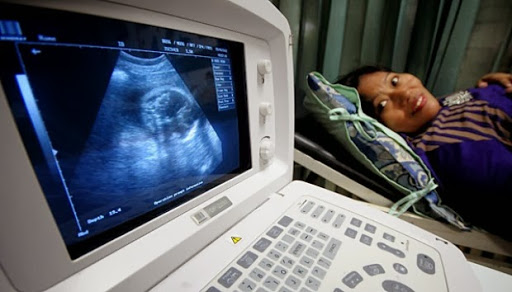

Memeriksakan kehamilan untuk mengetahui jenis calon bayi laki-laki atau perempuan dengan alat ultrasonografi (USG) menjadi trend pasangan suami istri di zaman modern ini. Selain untuk mengetahui kondisi kesehatan ibu atau janin, pemeriksaan ini dilakukan untuk menebak calon bayi apakah perempuan atau laki-laki? Di antara alasannya untuk menyiapkan nama calon bayi.